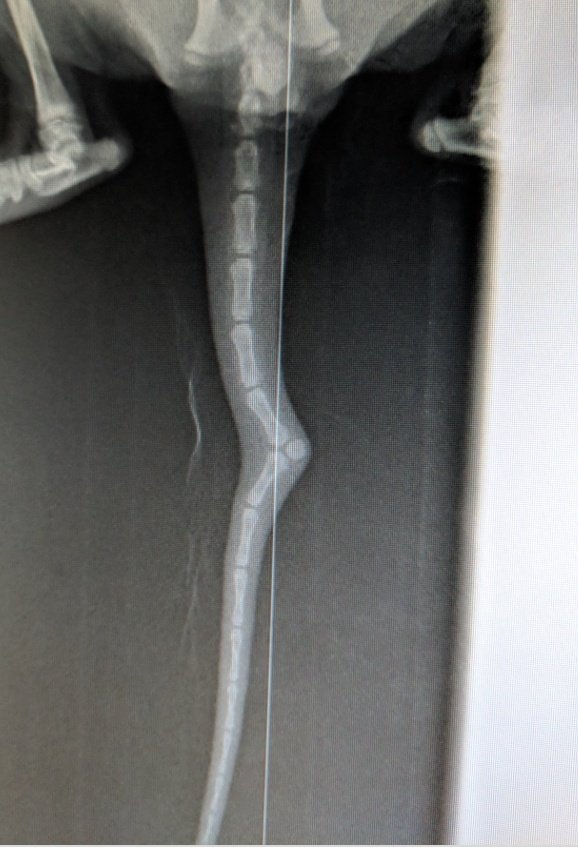

بالنسبة للذيل بالعادة بطيب لحاله هو، بس مرات بتقدر تحس بالكسرات مع الوقت بصير زي مفاصل انو بتلاقي الذيل زي حرف L صار. بس اكيد اذا تعالج صح بوقتها برجع كل اشي طبيعي.

في عنا شغلة مهمة تانية بالكسور بنشوفها كتير بس يوقع الحيوان من مكان عالي او يندعس. بدكم شوي شوي تحاولو تفتحو الفم "اذا ممكن". حتى تنتبهو ما تعطو اي اشي من خلال الفم. عشان كلو راح يدخل عالرئتين من هالكسر. (في حيوانات بتنولد بهالاعاقة اهم علامة الها الحليب بس يرضعو بطلع من الانف)